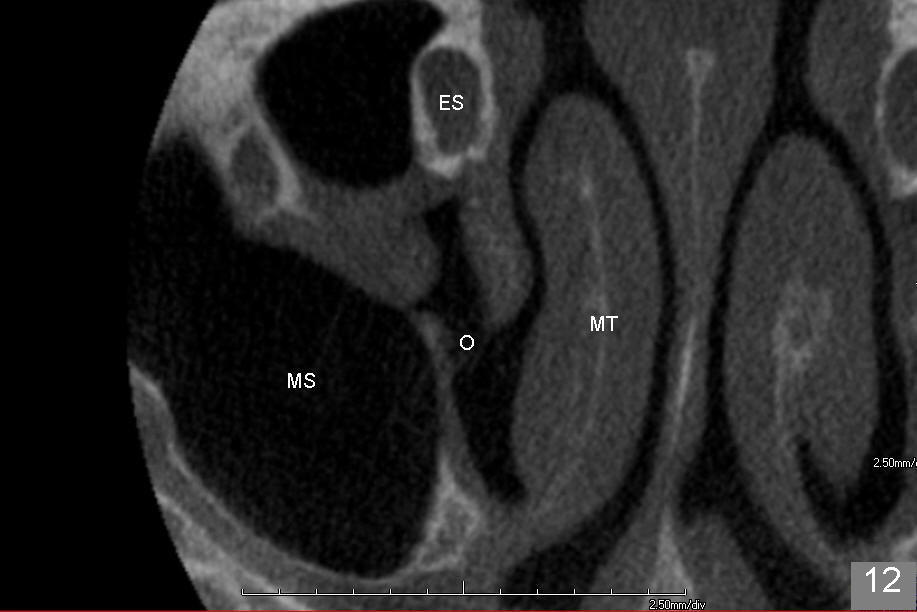

上颌窦手术后,病人即刻汇报患侧鼻塞,拍摄全景片,看不出来问题。给病人上颌窦术后医嘱,开喷鼻药(Afrin)和激素(Medrol Dosepak,减少水肿)。之后研究术前CT(图十至十二),但愿上颌窦分离内侧壁没有太过分。第二天鼻塞消失,病人并没有用喷鼻药,但是使用激素。